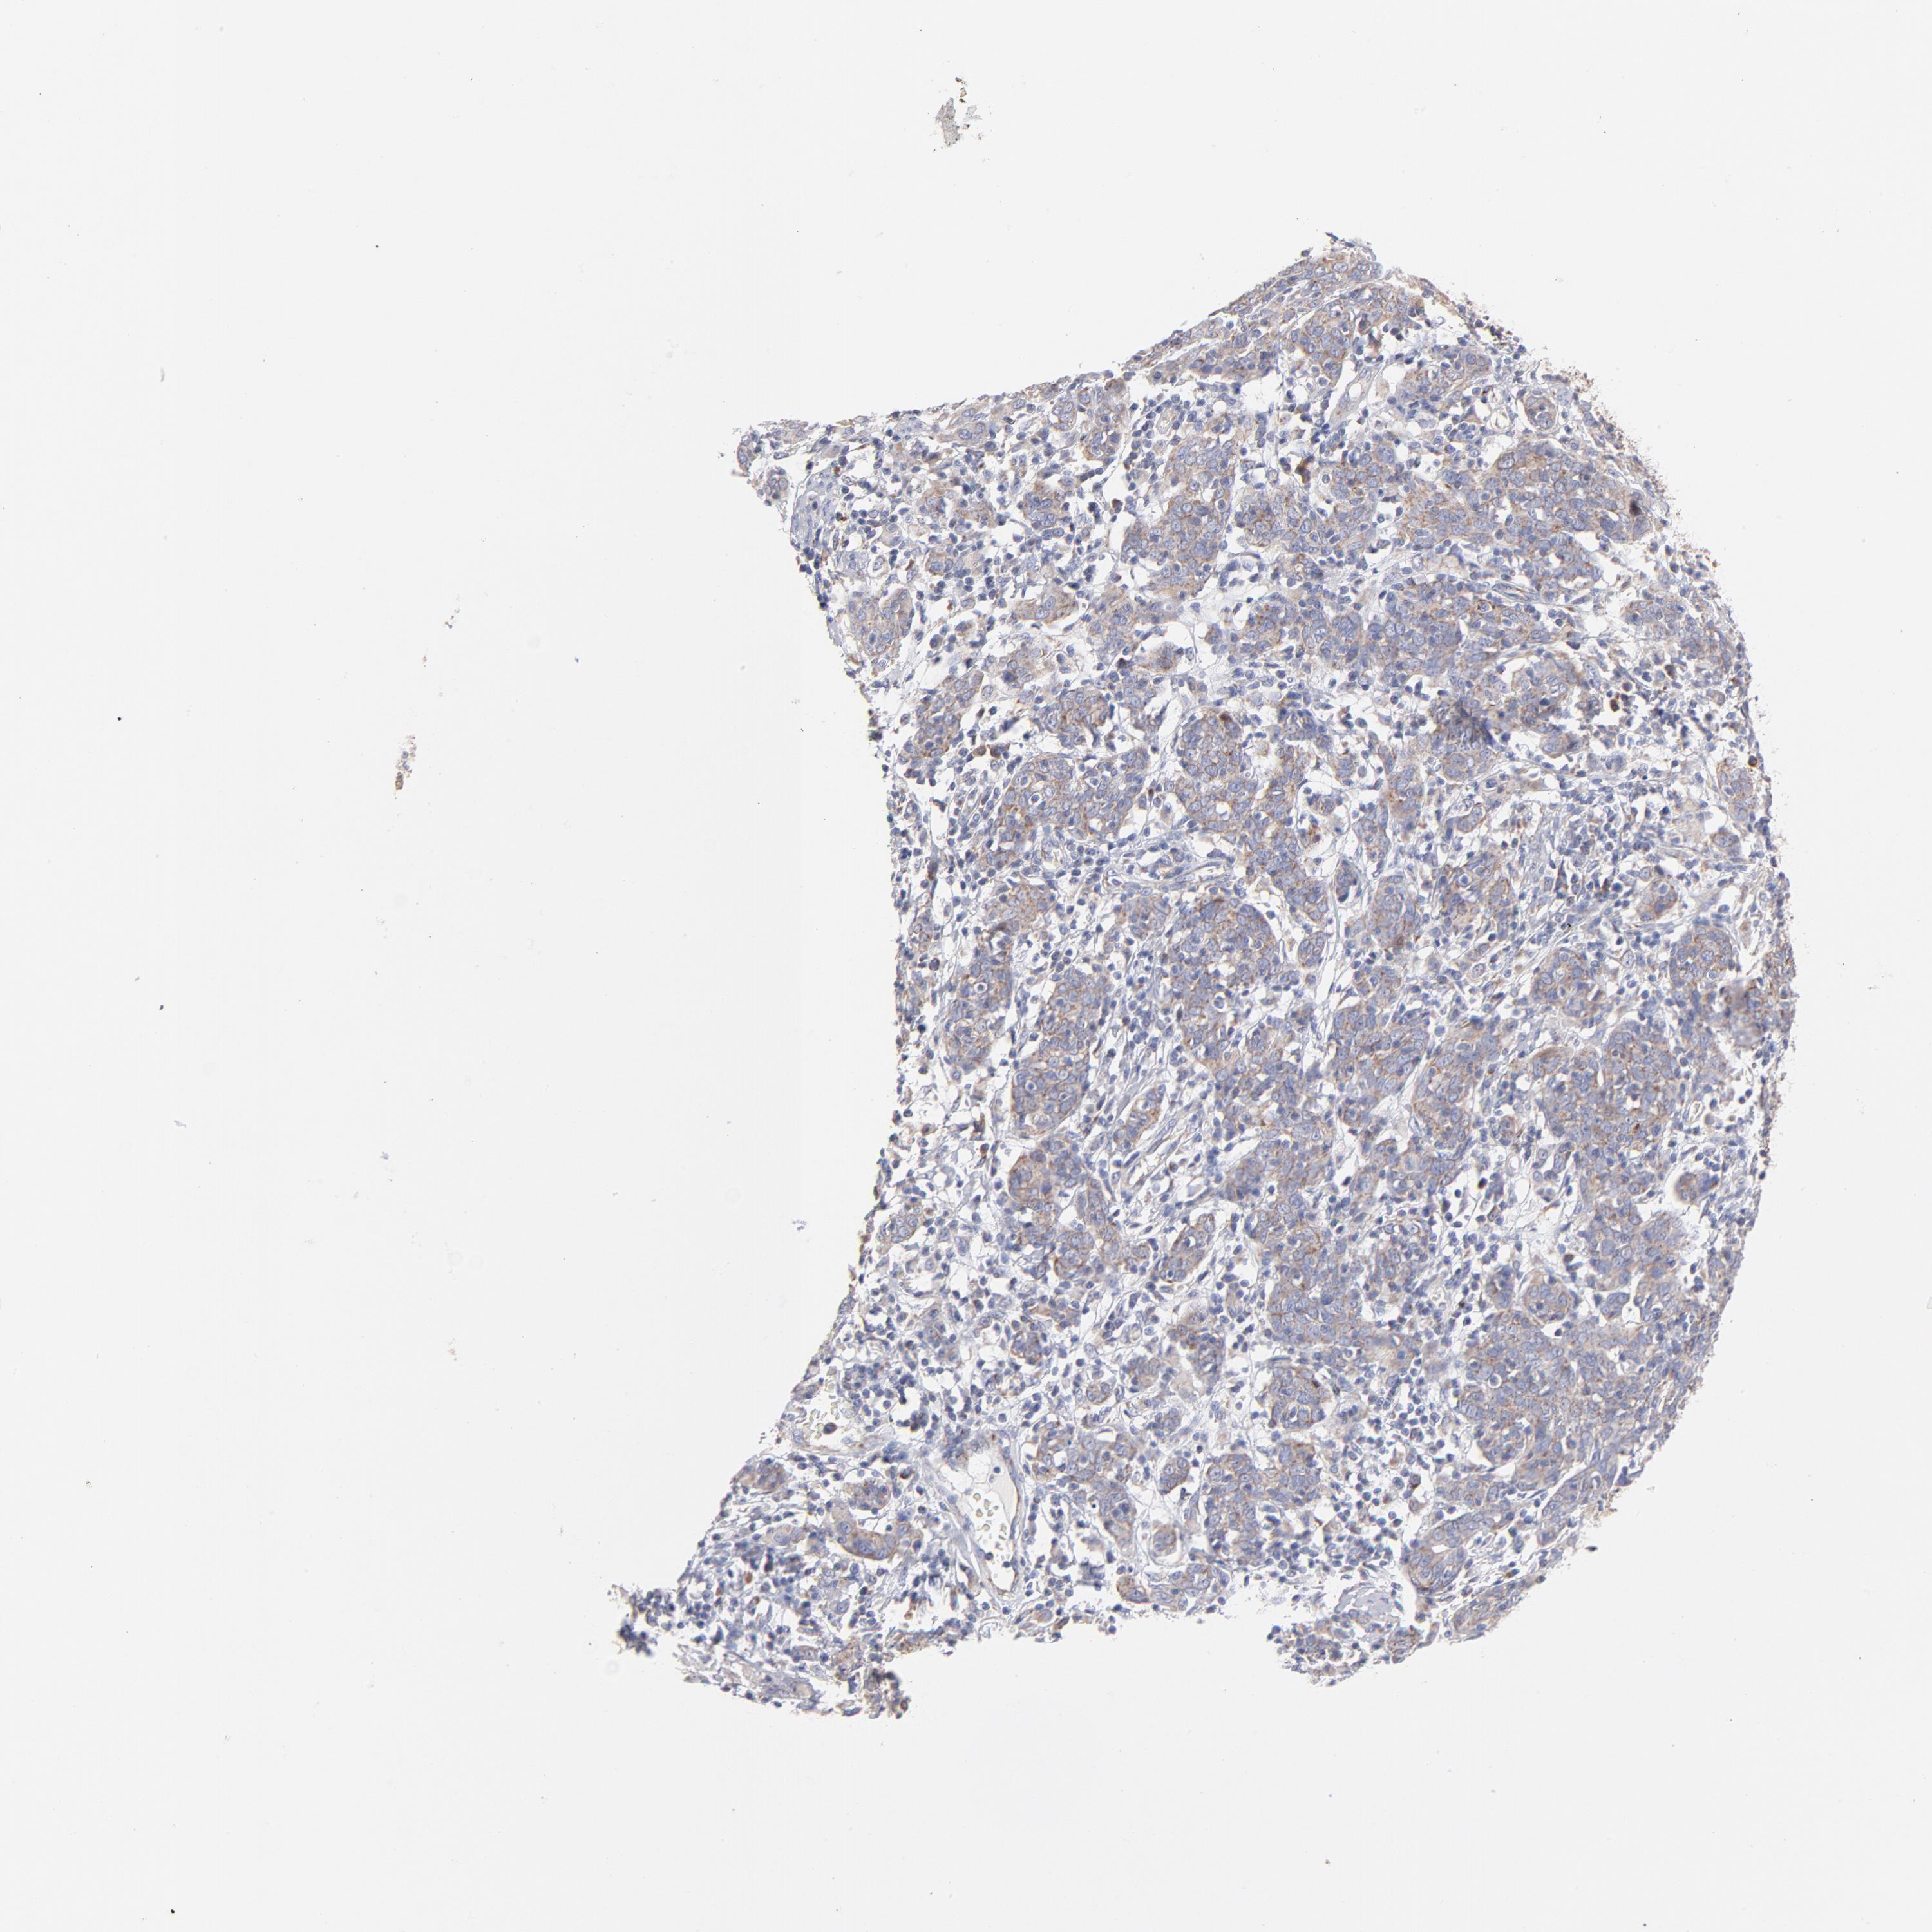

CERVICAL CANCER - Protein expressioni

A mouse-over function shows sample information and annotation data. Click on an image to view it in a full screen mode. Samples can be filtered based on level of antibody staining by selecting one or several of the following categories: high, medium, low and not detected. The assay and annotation is described here.

Note that samples used for immunohistochemistry by the Human Protein Atlas do not correspond to samples in the TCGA dataset.

Antibody stainingi

Antibody staining in the annotated cell types in the current human tissue is reported as not detected, low, medium, or high, based on conventional immunohistochemistry profiling in selected tissues. This score is based on the combination of the staining intensity and fraction of stained cells.

Each image is clickable and will lead to virtual microscopy that enables deeper exploration of all samples and also displays staining intensity scores, fraction scores and subcellular localization as well as patient and tissue information for each sample.

Antibody HPA003628

Staining

High

Medium

Low

Not detected

Intensity

Strong

Moderate

Weak

Negative

Quantity

>75%

75%-25%

<25%

None

Location

Nuclear

Cytoplasmic/membranous

Cytoplasmic/membranous,nuclear

Squamous cell carcinoma, NOS

Adenocarcinoma, NOS